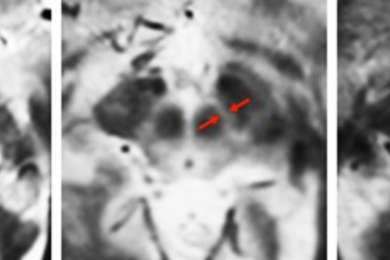

MRI sensor allows neuroscientists to map neural activity with molecular precision.